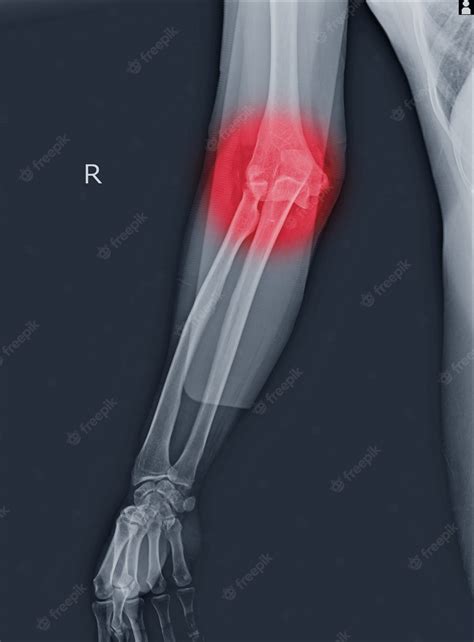

An elbow hairline fracture involves a small crack in one of the bones that make up the elbow joint. The elbow is a complex joint composed of three bones: the humerus (upper arm bone), the ulna (one of the forearm bones), and the radius (the other forearm bone). These bones are held together by ligaments, tendons, and muscles, which allow for a wide range of motion.

Hairline fractures are typically non-displaced, meaning the bone fragments remain in their normal position. This is in contrast to displaced fractures, where the bone fragments are separated and may require surgical intervention to realign.

• X-Rays: X-rays are the primary imaging tool used to diagnose hairline fractures. They can show the crack in the bone and help determine the extent of the injury.